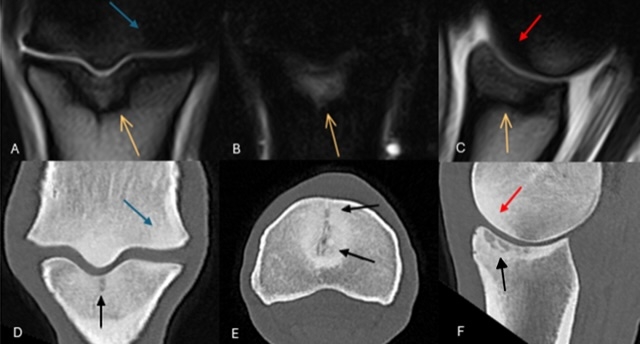

Figure 1: Frontal T2*W gradient echo (GRE) (A) and short tau inversion recovery (STIR) (B) and sagittal T2*W GRE magnetic resonance images (C) and frontal (D), transverse (E) and sagittal (F) computed tomographic (CT) reconstructions of the right forelimb

Figure 1: Frontal T2*W gradient echo (GRE) (A) and short tau inversion recovery (STIR) (B) and sagittal T2*W GRE magnetic resonance images (C) and frontal (D), transverse (E) and sagittal (F) computed tomographic (CT) reconstructions of the right forelimb of a 12-year-old showjumper.